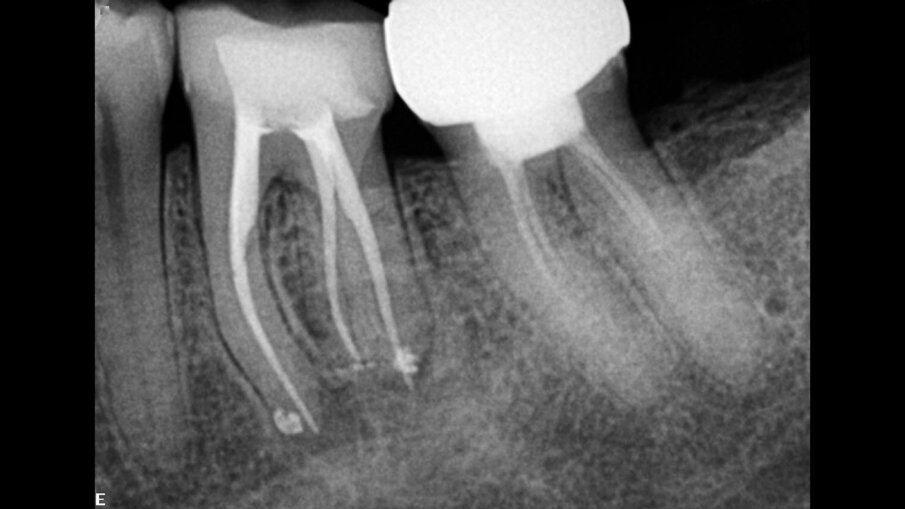

Sl.3: Retretman centralnog sekutića, nakon oblikovanja i obturacije oba kanala.

Fig. 3: Retreatment of the central incisor, after the shaping and obturation of both canals.